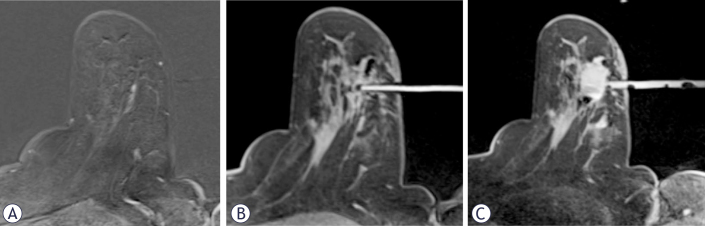

Abstract Image